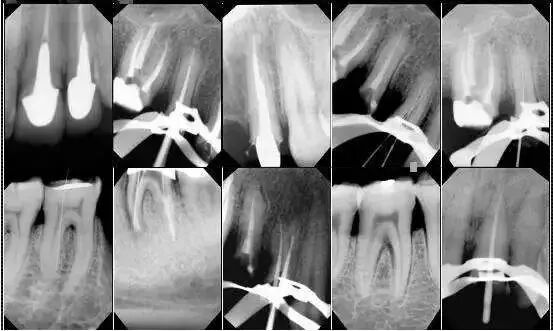

描述病情,其实并不像大家想的那么容易。也许你描述大半天,也不能描述到点上。在医院/诊所治疗时医生需要口腔镜深入口腔探查病因,为了拍出最能还原病情的照片,还需要单反相机、开口器、反光镜以及背景板等专业辅助器材用品。微信就诊病患一般只能提供一张随意拍的照片,并不能提供准确的信息供牙医参考,更何况牙医看病不仅仅是望诊,还有探诊,扪诊等。所以并不能在微信上进行就诊。